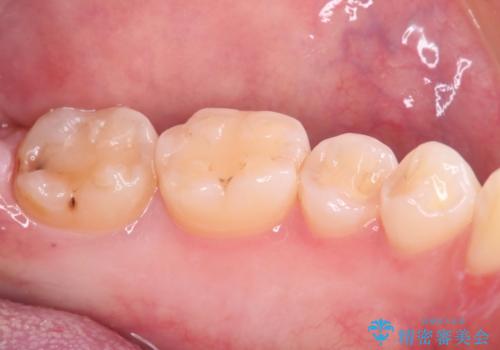

最新の症例

Latest cases